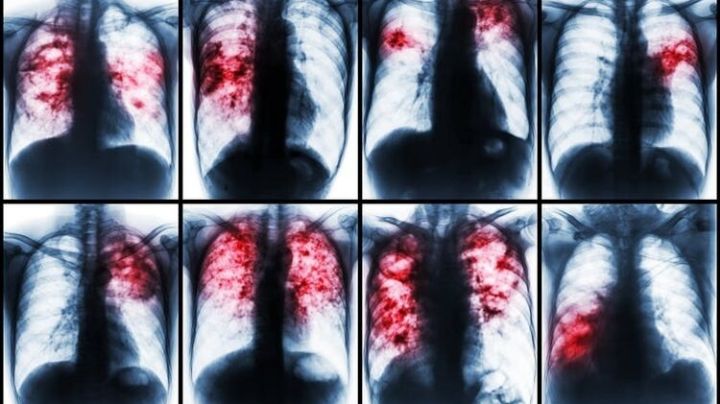

Casos de tuberculosis serán detectados en alta resolución en Laredo: viene nuevo equipo de rayos X

19/7/2025 | Los laredenses contarán en breve en el Departamento Municipal de Salud, con un nuevo aparato detector de tuberculosis, tecnología digital de gran resolución, pruebas rápidas, resultados también veloces